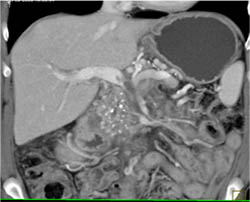

Cystic Pancreatic Mass- Cystadenoma- Pancreatic Mass Was Due to Angiomyolipoma (AML) - Leukemia